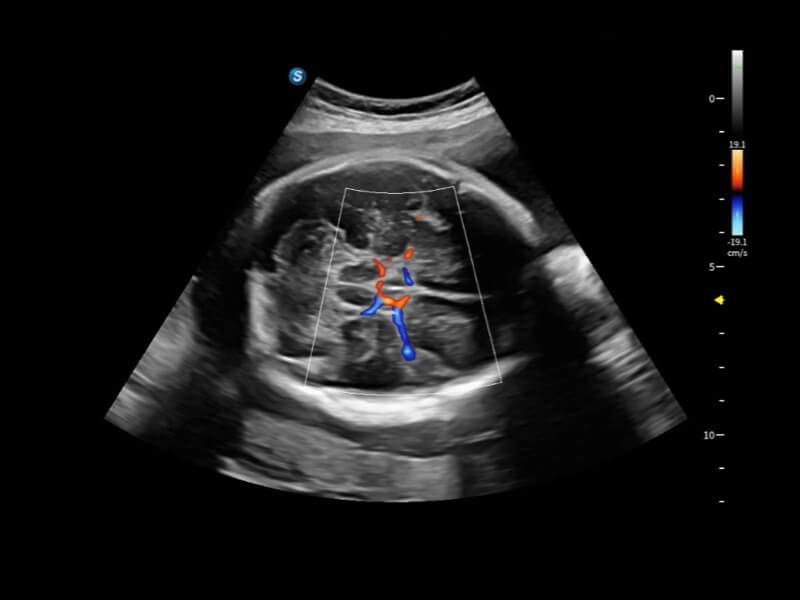

丰富的血流动力学检测技术,可在不同医疗场景中高效捕捉血流信号,助力临床诊疗。

在传统血流的基础上优化扫查和算法策略,能够更好的抑制组织信息,提炼红细胞运动信息,得到更高帧频,高灵敏度和分辨率的血流信号,还原更真实的血流动力学。

通过光照模型,使二维血流显示出立体的效果,增加血流的敏感性、成束性,减少外溢。可以和其他不同的血流技术联合使用,融合不同技术的优势。轻松应对微小血管,增强血流的立体效果,提升视觉敏感性。

通过创新的Matrix E自适应滤波算法,能有效滤除软组织和噪声信号,最大限度保留超低速微细血流的信号;结合超长时间域算法,极大提升细微血流的敏感性和空间分辨率,更真实的反应组织、包块的血流灌注情况。